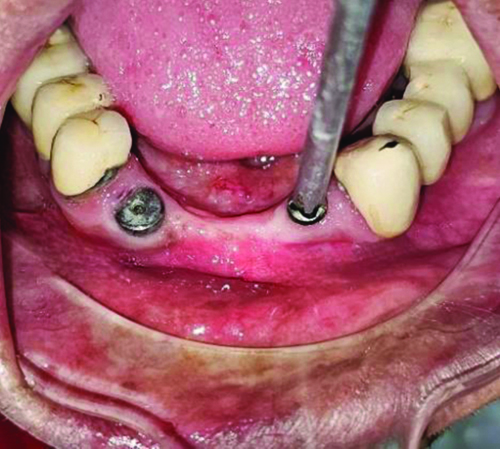

Using a high-speed handpiece and a carbide bur, a plus-shaped groove approximately 2 mm in depth was created from the center by extending the access hole of the former under copious irrigation until the screwdriver fitted snugly [Table/Fig-1] [2]. A high vacuum suction was employed to prevent any particles of the former from being swallowed by the patient. The screwdriver from the Typodont jaw set was autoclaved before use in the patient’s mouth [Table/Fig-2].

Screw driver used for the retrieval of former.

The gingival former was modified until the beak of the screwdriver fit snugly into the plus-shaped groove [Table/Fig-3]. Utmost care was taken during the grooving process, as excessive removal of the structure could lead to failure in fitting the screwdriver [Table/Fig-4]. The gingival former was modified until the beak of the screwdriver fit snugly into the plus-shaped groove [Table/Fig-3]. Careful attention was given during the grooving process, as excessive removal could result in failure to fit the screwdriver properly.

Snugly fitted screwdriver with modified gingival former.